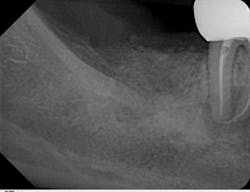

The old saying “you don’t know what you don't know” holds especially true in regard to 3-D radiology. You simply cannot gain the same amount of information from 2-D images. My main use for CBCT in the general dentistry practice is dental implant planning. In order to feel confident placing dental implants, I need this technology. I am able to identify cases that are appropriate for my skill level, as well as cases that are more difficult and should be referred. Whether a case will be tricky is not always obvious from a 2-D image and clinical exam. I also have not found a situation where less information was more beneficial than more information. I have never thought to myself, “I wish I didn’t have a 3-D scan of this patient.” Conversely, there were many times before buying my CBCT when I wished I had more than just a 2-D periapical (PA) or pan. The case shown in figures 1, 2, and 3 illustrates how the additional information CBCT provides aids in planning and placing dental implants.

Figure 3 tells a more complete story. The patient has a significant lingual concavity. I was unable to palpate the concavity clinically to realize its full extent. The 3-D image allows accurate measurement to the inferior alveolar nerve (IAN) and lingual concavity. It allows me to plan and place an implant of the appropriate length to avoid perforation of the lingual plate, which could lead to serious surgical complications.